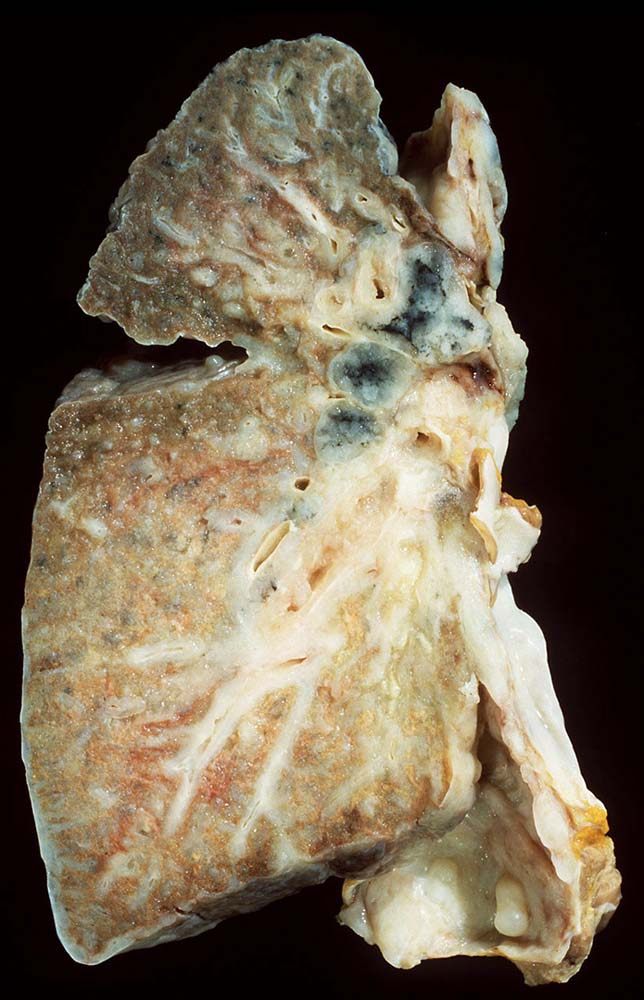

Das metastatische Wachstumsmuster von primären Bronchuskarzinomen und extrapulmonalen Tumoren innerhalb der Lunge ist variabel. Hämatogene Metastasen imponieren makroskopisch als multiple scharf begrenzte rundliche Knoten in allen Lappen meist in peripherer Lage. Der metastatische Befall von Lymphknoten kann durch direkte Tumorinfiltration durch den Primärtumor erfolgen (=per continuitatem) oder über die Lymphgefässe. Bei einer ausgeprägten lymphogenen Tumorausbreitung erscheinen subpleurale mit Tumor gefüllte Lymphgefässe makroskopisch als prominente weisse Streifen. Mikroskopisch lassen sich Tumorinfiltrate in peribronchialen und perivaskulären Lymphgefässen nachweisen (=Lymphangiosis carcinomatosa). Hepatozelluläre Karzinome metastasieren typischerweise in Form von Tumorembolien (> 1279) hämatogen in die Lunge.

• Sternförmiges Karzinom mit zentraler Vernarbung mit reichlich schwarzem Anthrakosepigment.